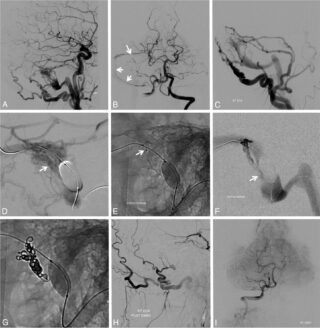

Endovascular Embolization

This inpatient procedure entails passing a small catheter (tube) from a blood vessel in the groin (or arm) up into the AVF, where glue or other material is injected. For many patients, this cures the AVF; in others, it is used in preparation for surgery or radiosurgery. If successful, it provides immediate protection against AVF rupture.